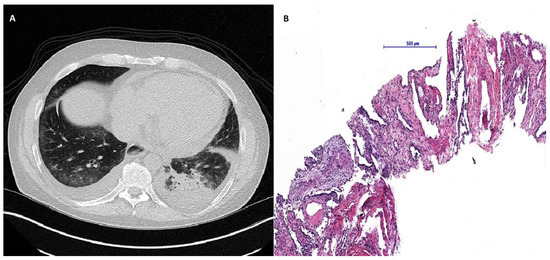

Due to active organ involvement, immunosuppressive therapy with rituximab (RTX) and mycophenolate mofetil (MMF) according to the Graz protocol [6] (Rituximab 500 mg: two intravenous infusions separated by 2 weeks every 3 months) was initiated as standard treatment with cyclophosphamide was refused by the patient. After immunosuppressive therapy and subsequent rehabilitation in May 2017, the patient’s initial symptoms improved with stable spirometry parameters and an ejection fraction of 55%; however, radiographic signs of the SSc-ILD did not improve and mRSS remained constantly at 11 points (Figure 1). Shortly after completion of the therapy, puffy fingers, acral necrosis of fingers and toes, and arthralgia of the ankles re-occurred and treatment with sildenafil was initiated. At the same time, spirometry parameters and echocardiographic findings (LVEF 50%) remained stable. In a follow-up visit in February 2018, NT-proBNP levels had increased significantly (18,287 pg/mL) accompanied by an increase of patient’s mRSS (14 points) (Figure 1) and persistent acral necrosis. Due to highly active multiple organ involvement and a high risk of disease progression, AHSCT was chosen as the next therapeutic option. In November 2018, the patient received AHSCT with a total of 2.08 × 106 CD34 + cells per kilogram of bodyweight positively selected stem cells. Conditioning regimen consisted of 148 mg/kg (= 8.8 g total dose) cyclophosphamide and 7.5 mg/kg of rabbit anti-lymphocyte globulin, and after continuous G-CSF stimulation from day five after AHSCT sustained neutrophil engraftment (absolute neutrophil count >0.5 G/L) was observed. Stem cell mobilization was performed with Granulocyte Colony-Stimulating Factor (10 microgram/kg bodyweight) for four days and at day 5 Plerixafor (0.24 mg/kg) was added due to insufficient CD 34 positive cell numbers in the peripheral blood. CD34+ enrichment and cryopreservation were done using the CliniMACS system (Miltenyi Biotec B.V. & Co. KG, 51429 Bergisch Gladbach, Germany) separating CD34 positive stem cells by magnetic beads from residual bone marrow cells. Eight days after AHSCT, the patient developed neutropenic fever and an increase of inflammatory parameters. HRCT of the lungs revealed ground glass opacities in both lower lobes with a consolidation in the left lower lobe (Figure 2). Lung function and mRSS (15 points) deteriorated (FVC 44.5% predicted, FEV1 35.1% predicted, FEV1/FVC ratio 72.75%, DLCO 40% predicted) (Figure 1). A consecutive bronchoscopy due to suspected pneumonia revealed no microbial growth in bronchoalveolar lavage. Despite intensified antibiotic and antifungal treatment, symptoms and radiographic findings did not improve. Subsequent percutaneous CT-guided lung biopsy revealed epithelioid cell pneumonia without a detectable pathogen (Figure 2).

High-dose corticosteroid therapy with prednisolon (1 mg/kg body weight) was initiated and immunoglobulins were added due to secondary immune thrombocytopenia. Symptoms of epithelioid cell pneumonia improved consecutively, but this therapy was followed by a hypertensive scleroderma renal crisis (SRC) with proteinuria and a significant decline in kidney function. After initiation of angiotensin converting enzyme (ACE) inhibitor therapy, proteinuria ameliorated and hypertensive blood pressure values normalized. The patient was discharged in good condition eight weeks after AHSCT.

Figure 2. (A) High-resolution computed tomography of the lungs revealed ground glass opacities in both lower lobes with a consolidation in the left lower lobe. (B) Histological presentation of changed lung parenchyma. Needle biopsy sample of lung parenchyma showed broad interalveolar septae with fibrous tissue and chronic inflammatory cells as well as reactive changed type 2 pneumocytes. Lower left part of the sample demonstrates merging epithelioid cell granulomas without necrosis within myofibroblastic proliferation.